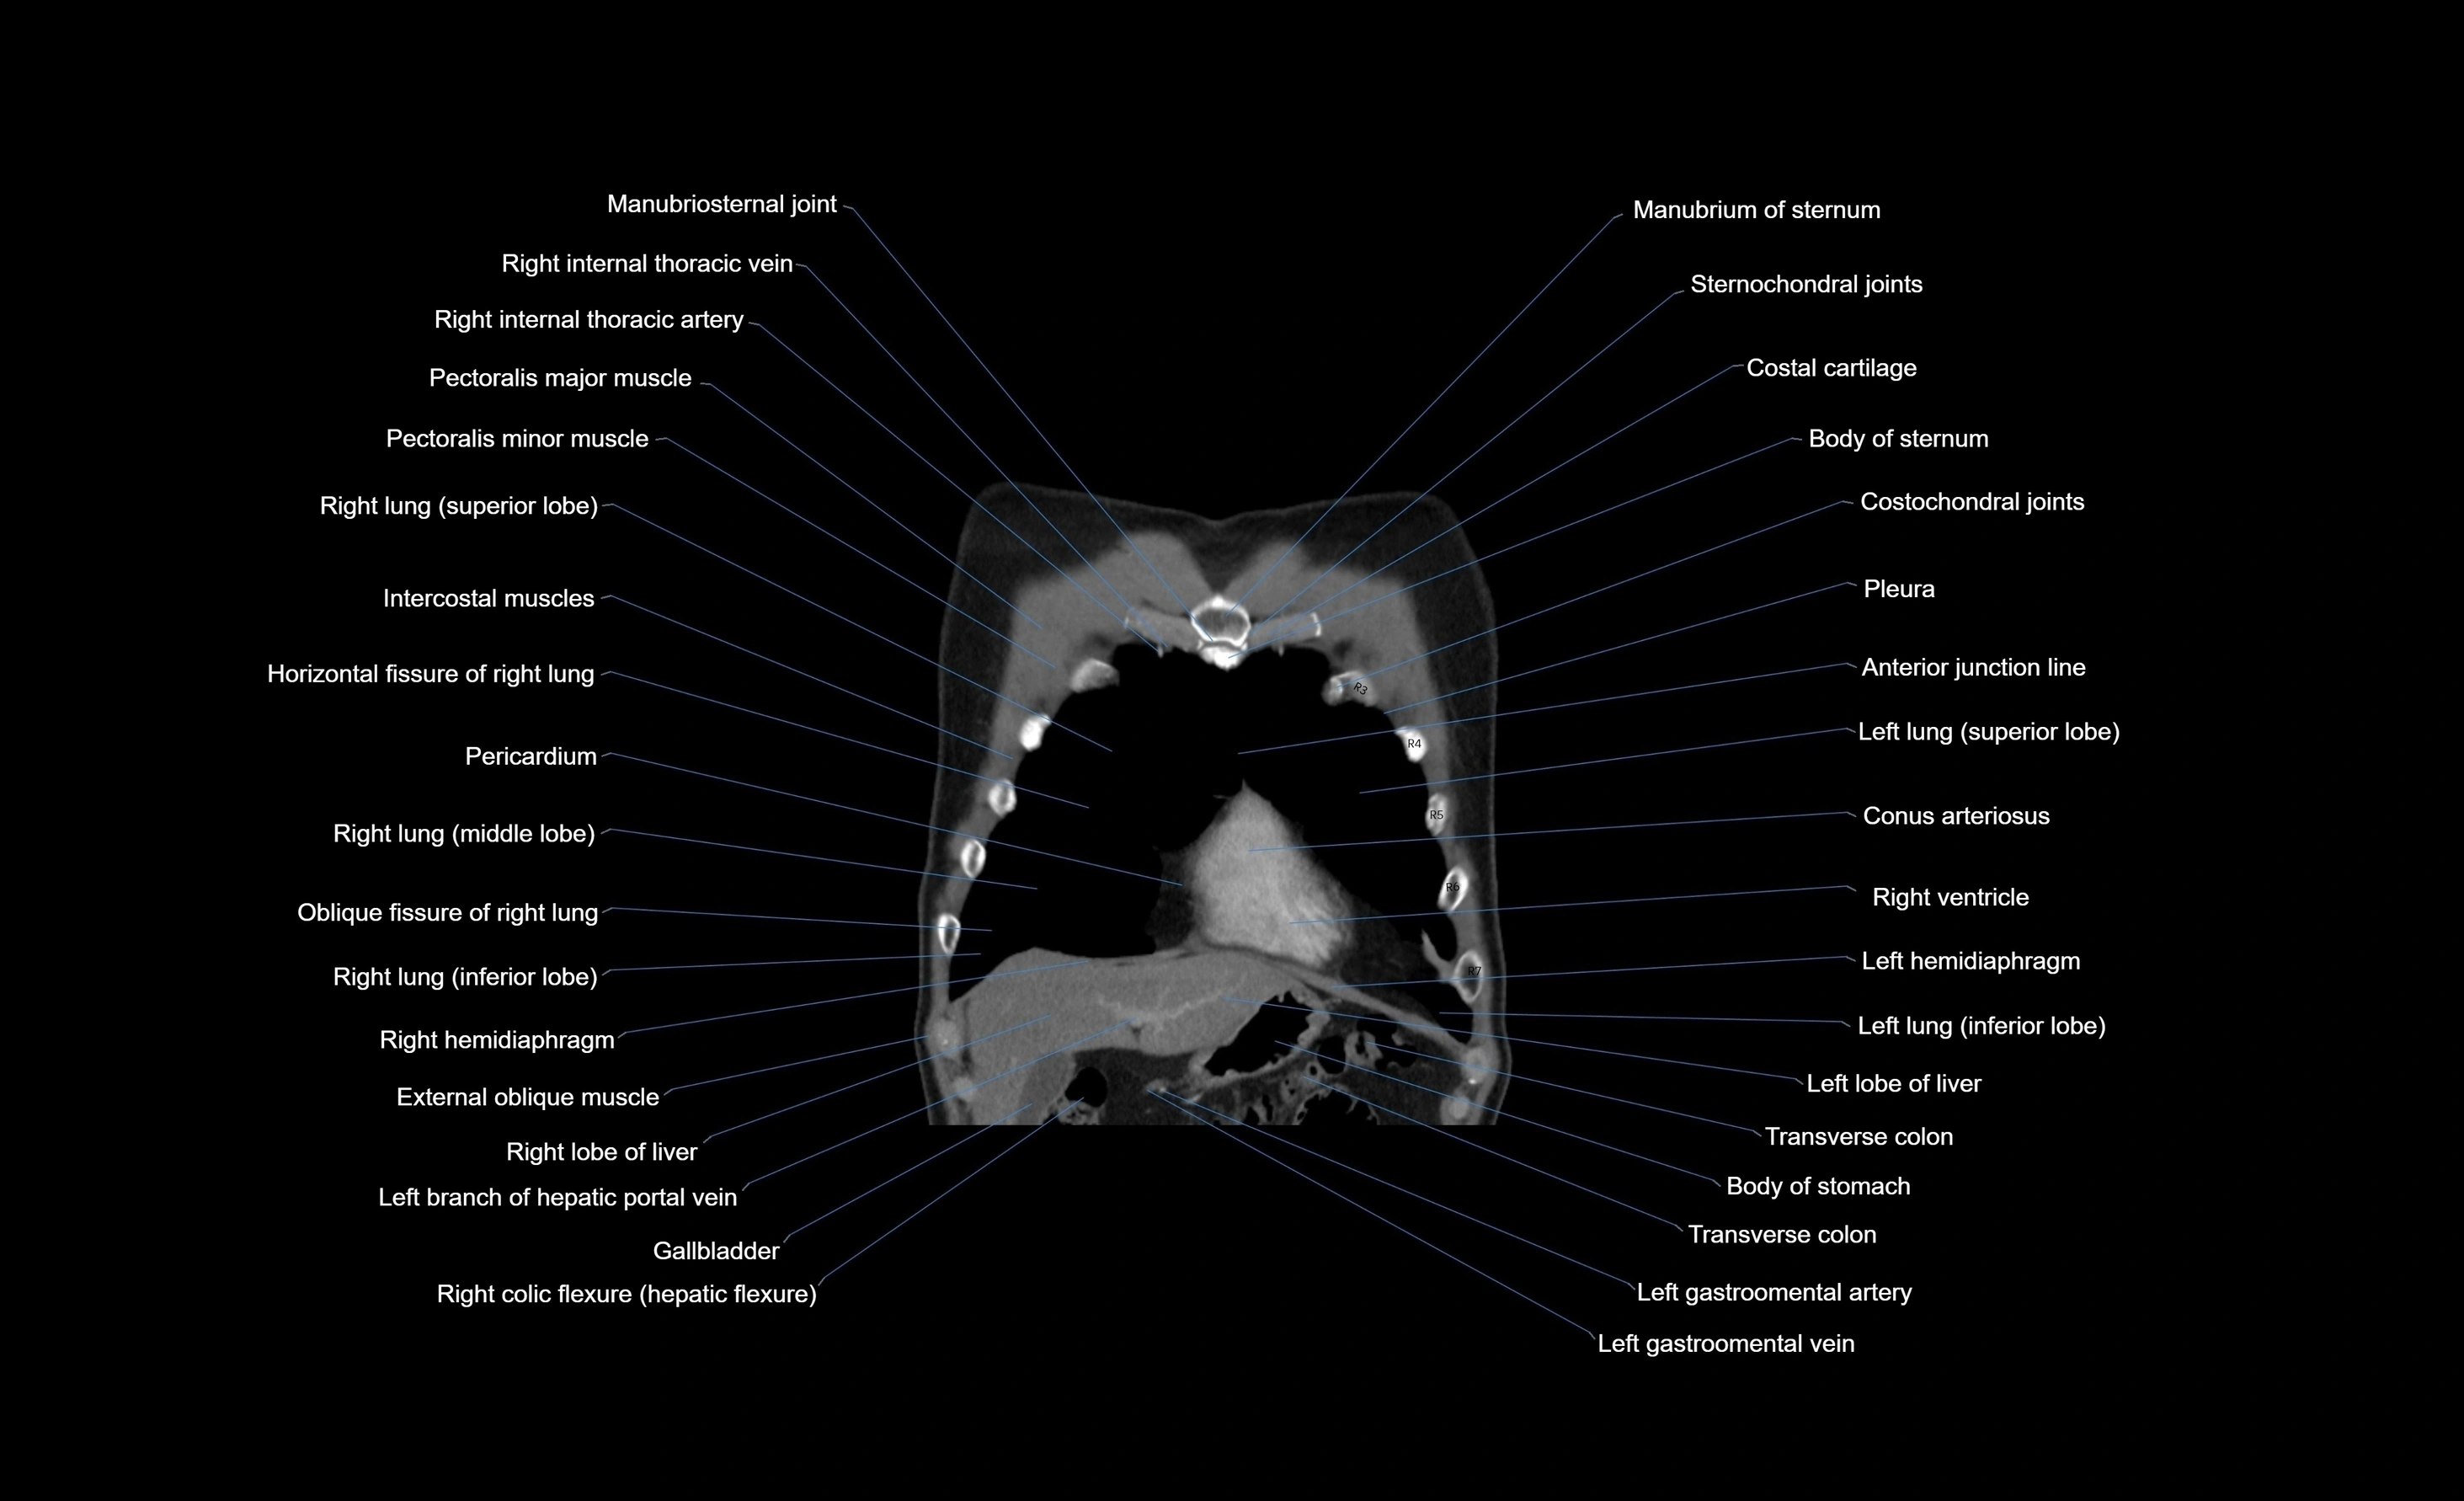

- Body of sternum

- Conus arteriosus

- Costochondral joints

- External oblique muscle

- Gallbladder

- Horizontal fissure of right lung

- Intercostal muscles

- Left hemidiaphragm

- Left lobe of liver

- Left lung (inferior lobe)

- Manubriosternal joint

- Manubrium of sternum

- Pericardium

- Pleura

- Right hemidiaphragm

- Right lobe of liver

- Right lung (inferior lobe)

- Right lung (middle lobe)

- Right lung (superior lobe)

- Right ventricle